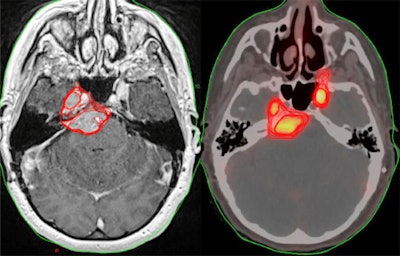

Patient Z is a female with a history of a grade 1 petroclival meningioma who was found to have progression on her most recent MRI brain scan with an increase in size from 3 x 1.5 cm to 3.4 x 1.4 cm. There was separate uptake on PET within the region of the left temporal lobe, which could relate to extension of the primary mass or separate focus of tumor. She was planned for 54 Gy of radiation in 30 fractions. Image courtesy of the International Journal of Radiation, Oncology, Biology, Physics.Overall, 344 contoured gross tumor volumes were included in the analysis. The median MRI volume for each physician ranged from 16.94 to 25.53 ccs. Conversely, the median PET volumes for each physician ranged from 2.09 to 8.36 ccs. The median PET volume was smaller for each physician, the researchers found.